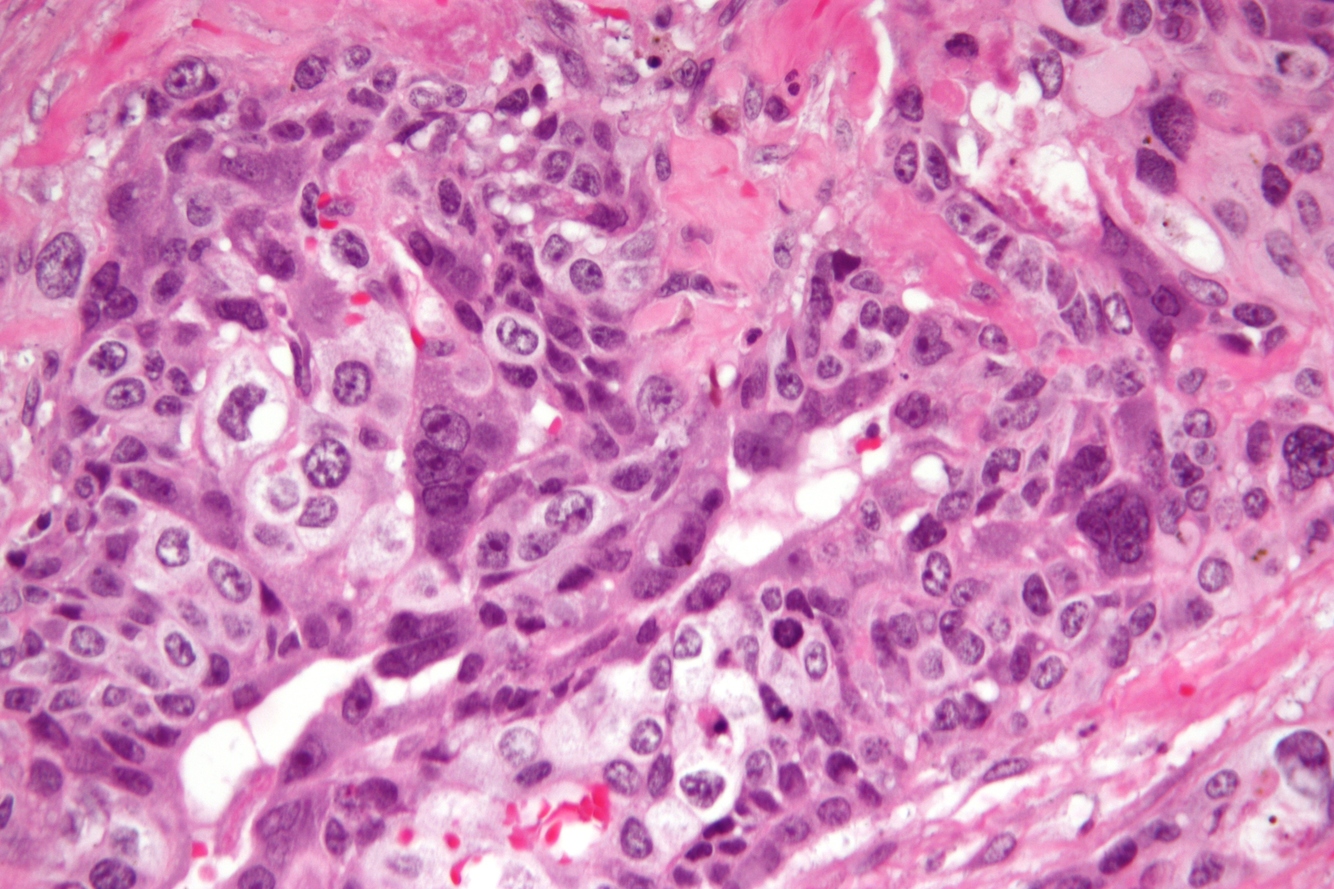

This patient presented with cysts on US and hCG > 1,000. Pathogenesis of this lesion?

Fertilization of empty egg (absent or non-functional DNA) by one or two sperm

(History suggests mole; histology shows trophoblastic hyperplasia = complete mole = 46XX or 46XY)

This patient presented with cysts on US and hCG > 1,000. Chromosome analysis would reveal:

69XX (or XY)

(History suggests mole; histology shows thin layer of trophoblasts suggesting partial mole = triploid)